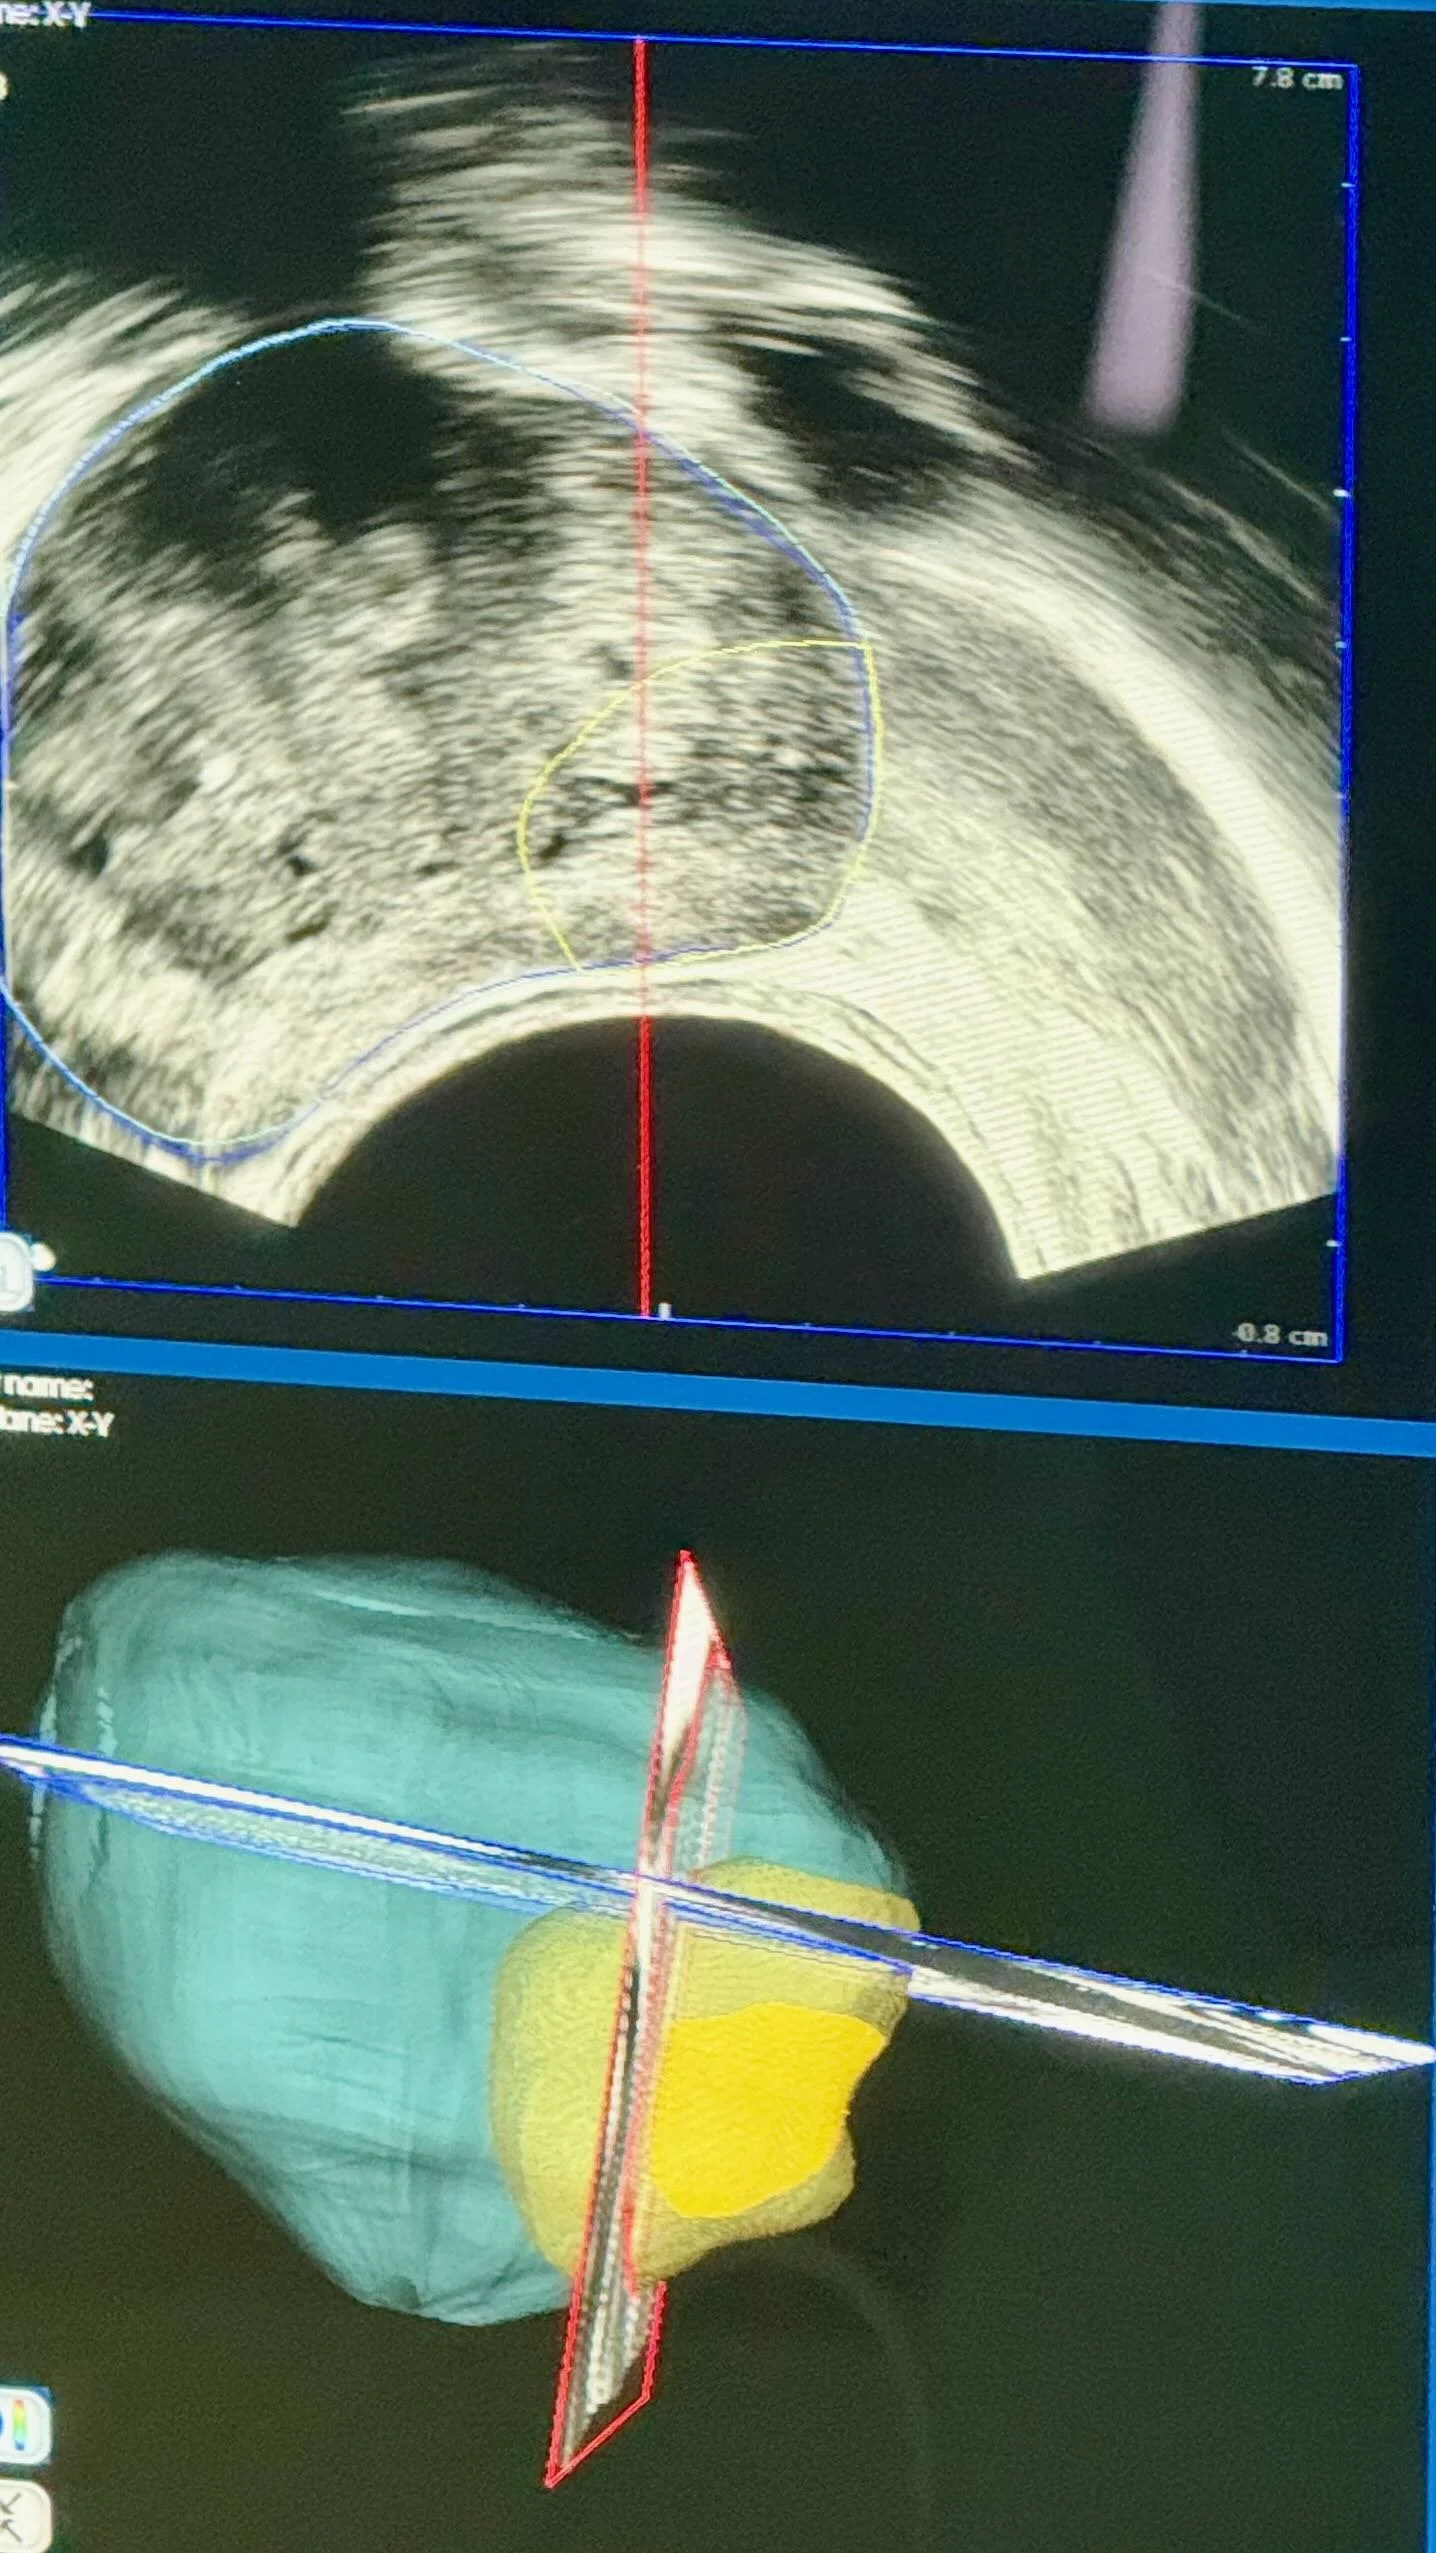

HIFUsion: MRI en echografie

Combineert 3D MRI-scans en echografie voor een nauwkeurige 3D-kaart van de prostaat, met tumorlokalisatie tot 1-2 mm.

Demonstratie van Focal One HIFU-behandeling met robotica en beeldvorming.